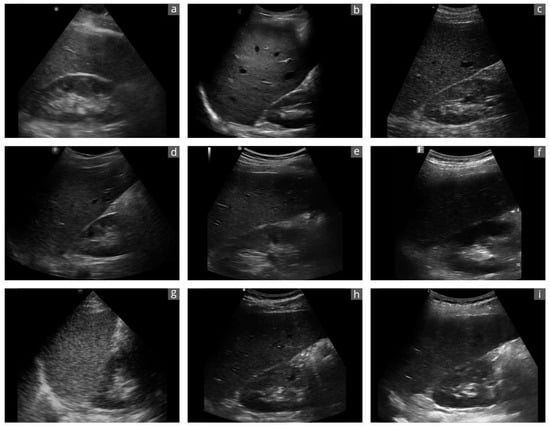

3.3. B-Mode Image Quality